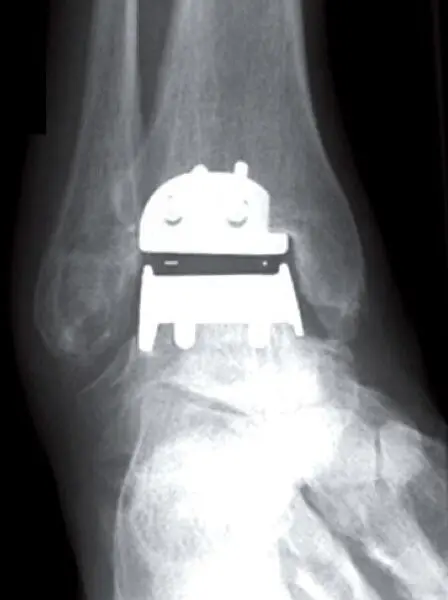

Proteza typu Hintegra stawu skokowego – widok od przodu Proteza typu Hintegra stawu skokowego – widok od przodu

Proteza typu Hintegra stawu skokowego – widok z boku

Proteza stawu skokowego typu Hintegra polega na wszczepieniu specjalnych implantów w miejsce uszkodzonej powierzchni stawowej. Dzięki temu Pacjent odzyskuje pełny zakres ruchu w stawie skokowym i może nie tylko normalnie chodzić, ale nawet biegać.